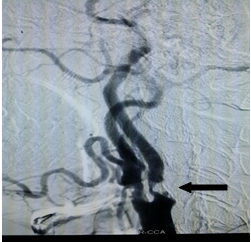

入院后,医生为其完善了所有检查,头颅MRI提示双侧小脑半球、桥脑右侧多发软化灶形成伴胶质增生、局限性脑萎缩,考虑脑梗塞后遗改变(图一);PWI-ASL提示双侧小脑半球、桥脑右侧低灌注(图二);DSA检查显示右侧颈内动脉起始部重度狭窄、狭窄程度大于90%,长 约5mm;2.右侧椎动脉开口中度狭窄,程度约45%,长约3mm,其余脑血管未见明显异常(图三)。

治疗方案:颈内动脉狭窄支架置入术(CAS)。

医生为患者实施右侧颈内动脉狭窄支架置入术治疗(CAS),术后脑DSA显示:造影后狭窄处明显改善,颅内血管供血有改善(图四)。

术前DSA(图三) 术后DSA(图四)